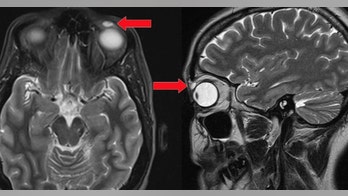

VISION AND HEARING August 15, 2018 Artist says parasitic worm in eye 'guided' his work The eerie painting depicts an image few of us would want to see in the mirror, let alone casting a shadow across our own field of vision: a pale, segmented worm slithering across an unblinking eyeball.